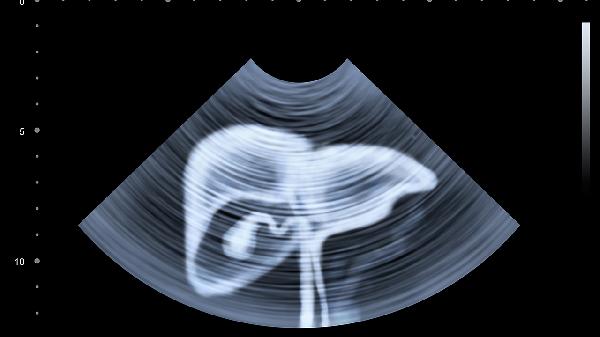

肝脏异常灌注是指肝脏血流动力学发生改变,导致肝组织血液供应过多或不足的病理状态,可能与肝动脉-门静脉分流、血管畸形、肝硬化、肝肿瘤等因素有关。肝脏异常灌注通常表现为肝功能异常、腹部不适、黄疸等症状,需通过影像学检查确诊。

肝脏血管畸形包括肝动脉瘤、门静脉海绵样变等,可导致局部血流分布异常。这类疾病可能引起肝区疼痛、消化道出血等表现。超声造影和磁共振血管成像有助于明确诊断,治疗方案包括血管内介入治疗或外科手术。